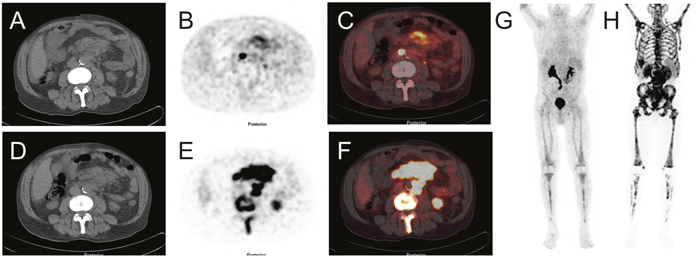

[68Ga]Pentixafor PET visualized PC-3 tumors with moderate contrast, for an example see Figure 1. Tumor uptake of [68Ga]Pentixafor was significantly lower compared to [18F]FDG (mean percentage injected dose/gram (%ID/g)mean 1.8 ± 0.6 and 5.8 ± 1.2, respectively, p < 0.001; mean %ID/gmax 2.5 ± 0.8 and 8.2 ± 1.8, respectively, p < 0.001), see Figure 2. No significant correlation was found between the tumor uptake of the two tracers (for %ID/gmean r = 0.176, p = 0.17; for %ID/gmax r = 0.136, p = 0.23). There was a significant correlation between mean metabolic tumor volume of [68Ga]Pentixafor and [18F]FDG (r = 0.723, p < 0.001). For [68Ga]Pentixafor mean tumor/muscle (T/M)PET, kidney/muscle (K/M)PET, liver/muscle(L/M)PET and tumor/blood (T/B)PET, kidney/blood (K/B)PET, liver/blood (L/B)PET was 2.66 ± 0.61, 6.57 ± 1.92, 3.62 ± 0.69, 1.01 ± 0.18, 2.34 ± 0.36, 1.37 ± 0.18, respectively and 4.34 ± 2.37, 7.10 ± 5.45, 2.30 ± 1.62, 0.26 ± 0.08, 0.44 ± 0.18, 0.14 ± 0.06 for [18F]FDG (Figure 3).

Figure 1: Image example: comparison of [68Ga]Pentixafor and [18F]FDG PET/CT in subcutaneous tumors (PC-3 cell line implanted in both flanks of a NMRI (nu/nu) mouse). Uptake of [68Ga]Pentixafor is lower compared to [18F]FDG. (A-C) [68Ga]Pentixafor (transaxial slices of (A) CT, (B) PET and (C) fused PET/CT); (D-F) [18F]FDG (transaxial slices of (D) CT, (E) PET and (F) fused PET/CT); maximum intensity projection (MIP) of [68Ga]Pentixafor (G) and [18F]FDG (H) showing different physiological tracer biodistribution of both tracers.